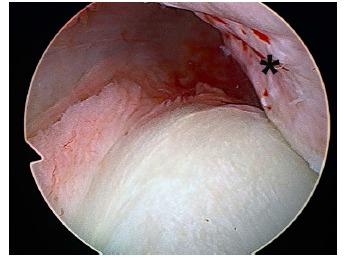

Arthroscopic osseous Bankart repair for chronic recurrent traumatic anterior glenohumeral instability.关节镜下骨性Bankart修复术治疗慢性复发性创伤性前盂肱关节不稳

Arthroscopic labral repair and capsular shift of the glenohumeral joint: technical pearls for a multiple pleated plication through a single working portal.肩关节镜下盂唇修复及盂肱关节囊移位:经单一工作通道进行多重折叠襞成形术的技术要点